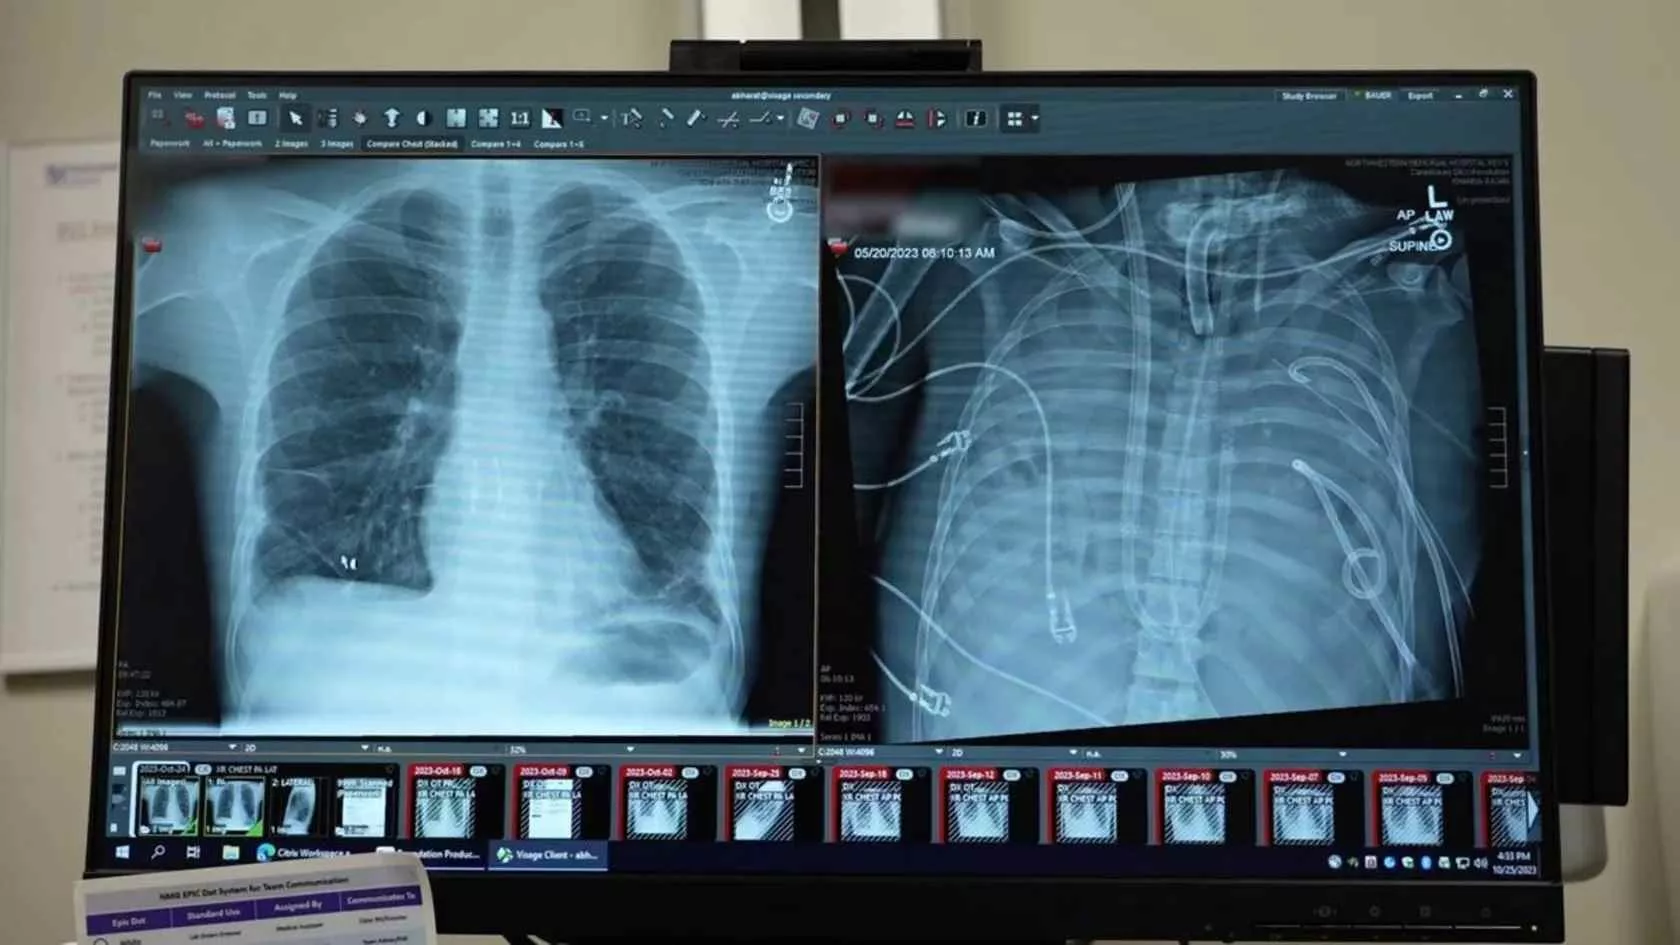

در قلب یکی از پیشرفتهترین مراکز پزشکی جهان، جایی که نبض فناوری با تپش زندگی درآمیخته است، داستانی در شرف وقوع بود که نه تنها مسیر درمان یک فرد، بلکه افق پزشکی مدرن را تغییر میداد. اتاق مراقبتهای ویژه (ICU) مملو از صدای ممتد دستگاههای مانیتورینگ بود؛ آوایی مصنوعی که در تقابل با سکوت مرگآور نبودنِ ریههای یک انسان قرار گرفته بود. این صحنه، روایتگر نبرد نهایی بیست و چند ساله، “دایمونت کلارک”، با نارسایی ریوی پیشرفته بود؛ نبردی که او در آن یکهوتنها بود و یارانش، پزشکان بودند که با سلاحی نوین به میدان آمده بودند: سیستمهای پیشرفته ریه مصنوعی برونبدنی (ECMO).

دایمونت، مانند هزاران بیمار دیگر، گرفتار بیماری مزمن انسدادی ریه (COPD) شده بود، اما وضعیت او به مرحلهای رسیده بود که هیچ درمان معمول، حتی تنفس با دستگاههای ونتیلاتور معمولی، قادر به اکسیژنرسانی کافی به بافتهای حیاتیاش نبود. ریههای او عملاً از کار افتاده بودند؛ اندامهایی که وظیفه حیاتی تبادل گازها را بر عهده دارند، تبدیل به تودههای غیرفعالی شده بودند که تنها بار سنگینی بر دوش کادر درمان بودند. در چنین شرایطی، پزشکان معمولاً تنها میتوانستند برای بیمار آرامش قبل از مرگ فراهم کنند. اما این بار، تیمی از متخصصان آمریکایی تصمیم گرفتند تا مرزهای ممکن را جابجا کنند؛ تصمیمی برای “نگهداشتن بیمار در آستانه مرگ با ریه مصنوعی”. این تلاش، صرفاً حفظ حیات نبود؛ بلکه نمایشی از مهندسی زیستی بود که طی آن، بدن بیمار به یک بیمارستان کوچک درونجسمی تبدیل میشد.

تیم پزشکی متوجه شد که ریههای دایمونت چنان آسیب دیدهاند که برای بهبودی نیاز به استراحتی مطلق دارند؛ استراحتی که باید طولانیتر از آن بود که بدن بتواند بدون حمایت کامل دوام بیاورد. اینجا بود که پای سیستم پیچیده حمایت تنفسی برونبدنی (Extracorporeal Membrane Oxygenation یا ECMO) به میان آمد.

ECMO فرآیندی است که در آن خون بیمار از بدن خارج شده، توسط دستگاهی (پمپ و اکسیژناتور) اکسیژنرسانی شده و دیاکسید کربن آن دفع میگردد و سپس خون تصفیهشده به بدن بازگردانده میشود. در حقیقت، این دستگاه وظیفه قلب و ریه بیمار را به طور همزمان یا فقط ریه (VA-ECMO یا VV-ECMO) بر عهده میگیرد.

در مورد دایمونت، تیم از VV-ECMO (Venovenous ECMO) استفاده کرد، زیرا قلب او هنوز کار میکرد، اما ریهها ناتوان بودند. خون وریدی (کماکسیژن) از بیمار خارج میشد، در دستگاه اکسیژنگیری میشد و سپس به سیستم وریدی بازمیگشت، در حالی که ریههای دایمونت در سکوت مطلق قرار گرفتند تا شاید فرصتی برای ترمیم بیابند. این فرآیند برای بیش از سه هفته ادامه یافت، رکوردی در مدیریت بیماران با این شدت آسیب.

فناوری ریه مصنوعی که دایمونت از آن بهره برد، اوج مهندسی پزشکی در حوزه حمایتی حیات است. این سیستم، برخلاف ونتیلاتورهای سنتی که هوا را مستقیماً به ریهها پمپ میکنند، یک شریان و ورید مصنوعی خارج از بدن ایجاد میکند.

ساختار علمی ریه مصنوعی (ECMO)

ECMO سیستمی از اجزای به هم پیوسته است که یک حلقه بسته را تشکیل میدهند:

- کانولها (Catheters): لولههایی مخصوص که از طریق آنها خون بیمار خارج و وارد سیستم میشود. در VV-ECMO، خون از طریق وریدهای بزرگ (معمولاً ورید ژوگولار یا سابکلاوین) گرفته شده و به سیستم بازگردانده میشود.

- پمپ سانتریفیوژال (Centrifugal Pump): این دستگاه جایگزین نیروی قلب میشود و جریان خون را با سرعتی کنترلشده به جلو میراند. این پمپها به گونهای طراحی شدهاند که کمترین آسیب مکانیکی را به سلولهای خونی وارد کنند.

- اکسیژناتور (Oxygenator) یا “ریه مصنوعی”: این قلب سیستم است. خون در تماس با یک غشای نیمهتراوا (معمولاً از جنس فیبرهای توخالی پلیمری) قرار میگیرد. در یک سمت غشا، خون جریان دارد و در سمت دیگر، گازهای پزشکی (مخلوط اکسیژن خالص و دیاکسید کربن) پمپاژ میشود. بر اساس قانون انتشار فیک (Fick’s Law of Diffusion)، اکسیژن به داخل خون نفوذ کرده و دیاکسید کربن از خون خارج میشود.

- مبدل حرارتی (Heat Exchanger): دمای خون برای حفظ ترمورگولاسیون بدن بیمار تنظیم میشود.

- سیستم مانیتورینگ: شامل حسگرهایی برای اندازهگیری فشار، سرعت جریان خون، میزان اکسیژنرسانی (SatO2) و PCO2.

تفاوت حیاتی ECMO با ونتیلاتور مکانیکی

بزرگترین تفاوت در عمق حمایت است:

ویژگیونتیلاتور مکانیکیECMO (به ویژه VV-ECMO)مکان عملکرددرون بدن (هوای تنفسی به ریه تحویل داده میشود)خارج از بدن (خون خارج شده، تصفیه و بازگردانده میشود)نقش در ریهحمایت مکانیکی از انبساط و انقباض ریهحذف کامل بار کار ریه (استراحت مطلق فیزیولوژیک)هدف اصلیتسهیل تهویه (رساندن اکسیژن و دفع CO2)جایگزینی کامل عملکرد تبادل گاز ریهاثر بر فشارمیتواند باعث آسیبهای فشاری (Barotrauma) شودفشار خارجی وارد بر ریه را به حداقل میرساند

توضیح پیشرفته علمی: در ECMO، ما از مکانیسم “دیافیلتراسیون” (برای دفع مایعات اضافی) و “انتشار گاز” برای مدیریت گازهای خون استفاده میکنیم. میزان حذف CO2 (Sweep Flow) و میزان اکسیژنرسانی (Gas Flow) پارامترهای کلیدی هستند که به طور مداوم تنظیم میشوند تا محیط هموستاز خون حفظ شود. هدف این است که اندامهایی که به شدت تحت استرس هستند، به خصوص ریهها، از نظر متابولیک غیرفعال شوند تا انرژی بدن صرف ترمیم بافتهای آسیبدیده شود.